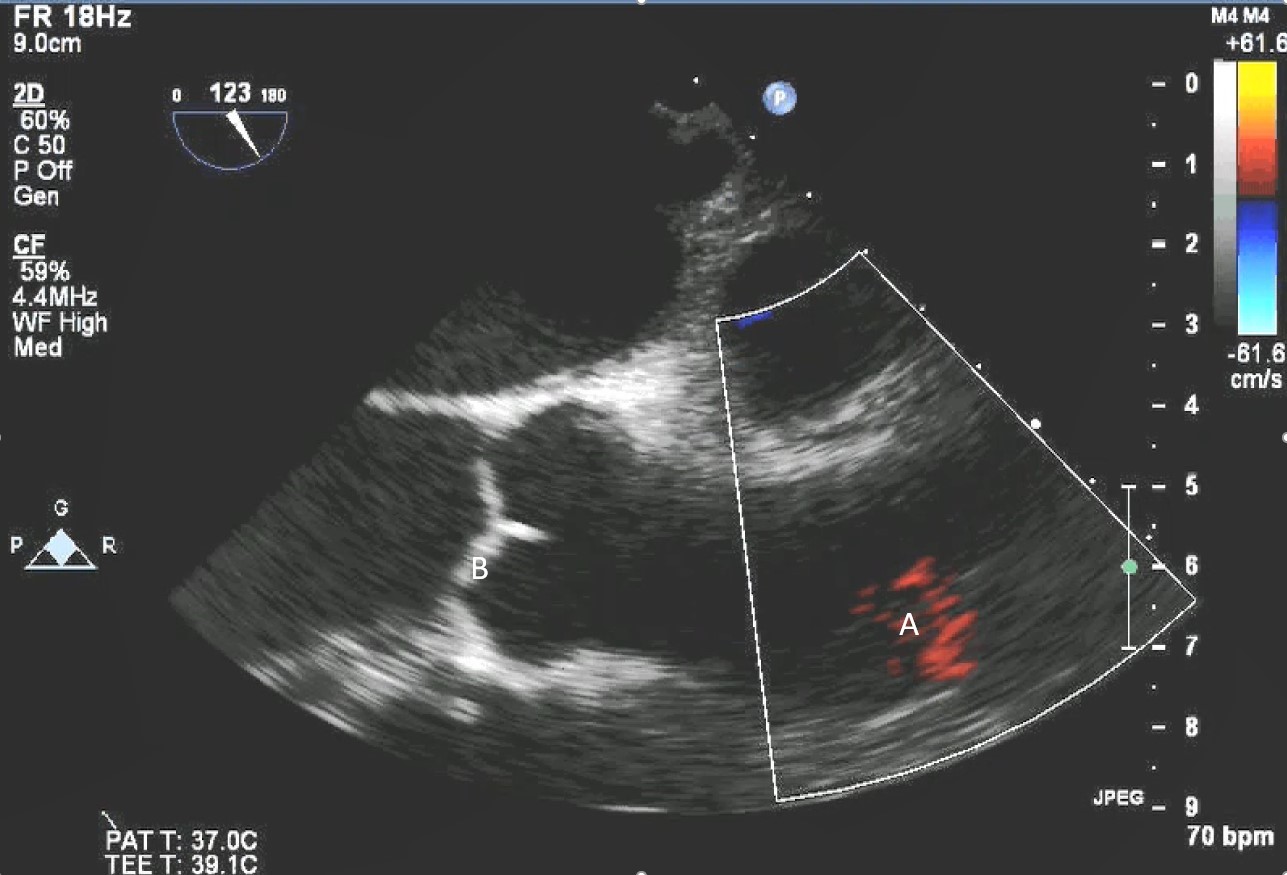

The intra-aortic balloon pump is a percutaneously placed counter pulsation device which helps in decreasing afterload as well as augmenting coronary perfusion. Initially developed in the 1960s it is the oldest MCS device and given its simplicity, cost effectiveness, and ease to implant and explant, it is the most commonly used temporary support device [6]. Although it is typically placed in the cardiac catheterization lab under fluoroscopic guidance, TEE can be utilized to help in its placement in the intubated patient in the intra-operative setting. The femoral artery is the most common site of placement however they can on occasion be placed in alternative sites such as the axillary artery or directly into the aorta [7, 8]. When placed via the femoral artery, it is threaded over a guidewire. TEE can be used to visualize both the guidewire as well as the tip of the IABP catheter during placement (Fig. 1) [9]. Ideal positioning of the balloon tip is 1–2 cm distal to the left subclavian artery to derive maximal hemodynamic benefit [10]. Positioning can be confirmed by visualizing the descending aorta and then withdrawing the TEE probe until the left subclavian artery and aortic arch are visualized. Upon activation of the balloon pump the gas filled balloon will cause shadowing and reverberation artifacts (Fig. 2). Its presence can be used as confirmation of proper function of the device. If these artifacts are not seen or bubbles are visualized in the aorta, rupture of the IABP should be suspected [9]. In addition to hemodynamic monitoring with a Swan-Ganz catheter, TTE can be used to monitor LV function after IABP placement and can help guide weaning of IABP support. It can also visualize any new or worsening aortic regurgitation. Given that IABPs work by reducing afterload, on rare occasions they can precipitate dynamic outflow tract obstruction and paradoxically worsen cardiogenic shock. Examples include patients with a relatively preserved basal or septal myocardial function in scenarios such as takotsubo cardiomyopathy or acute myocardial infarctions. Doppler imaging and color flow doppler can be used to identify such scenarios [11].

Fig. 1.TEE demonstrating IABP in descending aorta (A).

TEE demonstrating IABP in descending aorta (A) with reverberation artifact seen behind it upon activation (B).